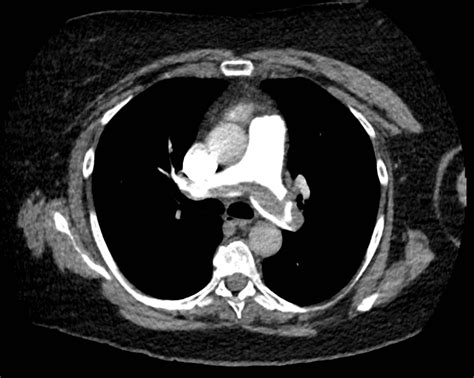

Pulmonary embolism (PE) is a serious medical condition that occurs when a blood clot, typically from the legs, travels to the lungs and blocks an artery. This blockage can be life-threatening if not promptly diagnosed and treated. One of the most widely used tools for assessing the likelihood of pulmonary embolism is the Pulmonary Embolism Wells Score. This scoring system helps healthcare professionals determine the probability of PE in patients presenting with symptoms suggestive of the condition.

• Diagnostic Testing: Based on the risk category, appropriate diagnostic tests are ordered. For example, patients with a high probability score may undergo immediate imaging studies, while those with a low probability score may require further clinical evaluation.